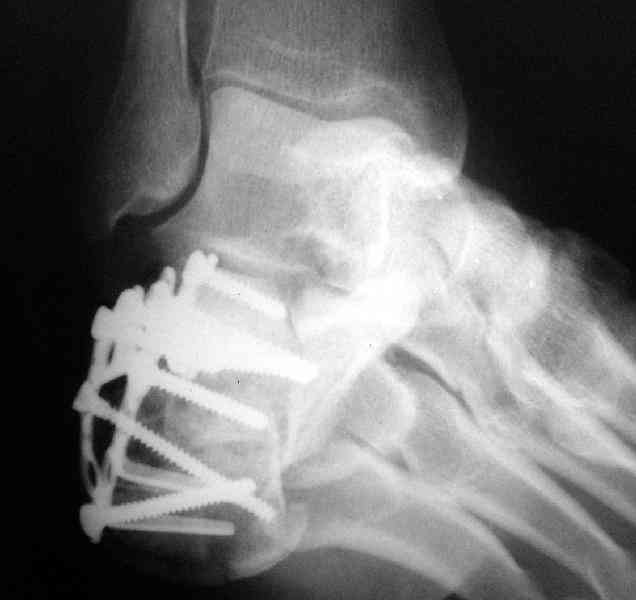

Пяточной пластиной

Открытый и закрытый способы лечения.